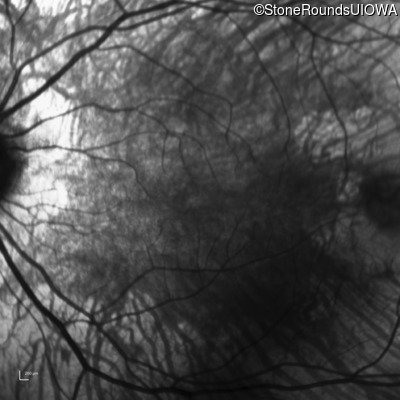

Infrared Fundus Photograph - Left - 20/32 -2

Exemplar